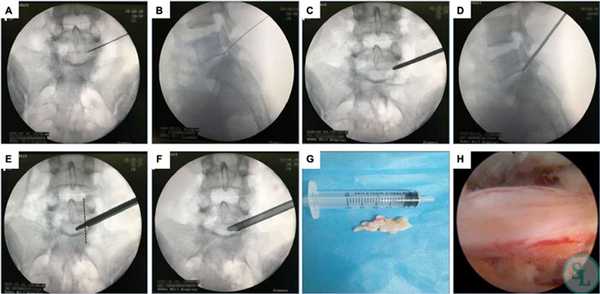

- В созданное отверстие под контролем ЭОП в безопасную зону позвоночного пространства вводится дилататор (расширитель), затем по нему вводится рабочая гильза, и уже через гильзу устанавливают трубку эндоскопа. В основном приборе подключают камеру и световод.

- Под многократно увеличенным видеонаблюдением, используя сменные инструменты, которые помещаются внутрь эндоскопа, хирург выполняет необходимые манипуляции. Специалист аккуратно удаляет источник компрессионного синдрома, например, остеофиты костными кусачками, грыжу диска микрощупом. Таким образом, достигается декомпрессия нервов или сосудов, которые смогут восстановиться уже в скором времени.

- Иссеченные структуры выводятся через отсек эндоскопической системы, полость позвоночного канала тщательно промывается физиологическим раствором от хирургического «мусора». Далее прибор извлекается, после чего ранку дезинфицируют и накладывают на нее несколько швов.

- Через разрез в безопасную зону позвоночного пространства вводится расширитель под контролем ЭОП. По нему погружается рабочая гильза, сквозь которую проводят трубку эндоскопа. Ее диаметр составляет 6-8 мм. Подключают светодиод и камеру, моментально начинающую трансляцию изображения на монитор.

- Под многократным увеличением с помощью специальных инструментов, вводимых в операционное поле через трубку эндоскопа и сменяемых в ходе операции, нейрохирург выполняет резекцию патологически измененных тканей. Он последовательно устраняет образование, ставшее причиной развития компрессионно-вертебрального синдрома. Так для резекции костных остеофитов используются специальные кусачки, а для удаления грыжи межпозвоночного диска - микрощуп.

- Удаленные фрагменты выводятся из организма посредством специального отсека эндоскопической системы, а образовавшаяся полость тщательно промывается физиологическим раствором.

- Оборудование извлекают, а на послеоперационную рану накладывают швы.